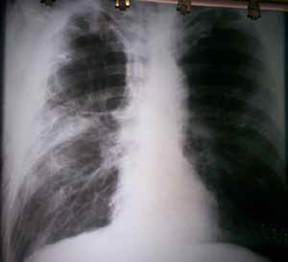

Se retiró la sonda torácica obstruida y se practicó una nueva pleurotomía mínima baja, manteniéndose con una aspiración negativa a -20 cm de agua. El derrame disminuyó considerablemente, pero, al suspender la aspiración negativa, el pulmón colapsó nuevamente. El paciente se negaba a otros procedimientos quirúrgicos, por lo que, mediante consulta con el grupo de especialistas, se decidió optar por una pleurodesis con talco por la sonda, después de la cual, se logró mantener expandido el pulmón (figura 3).